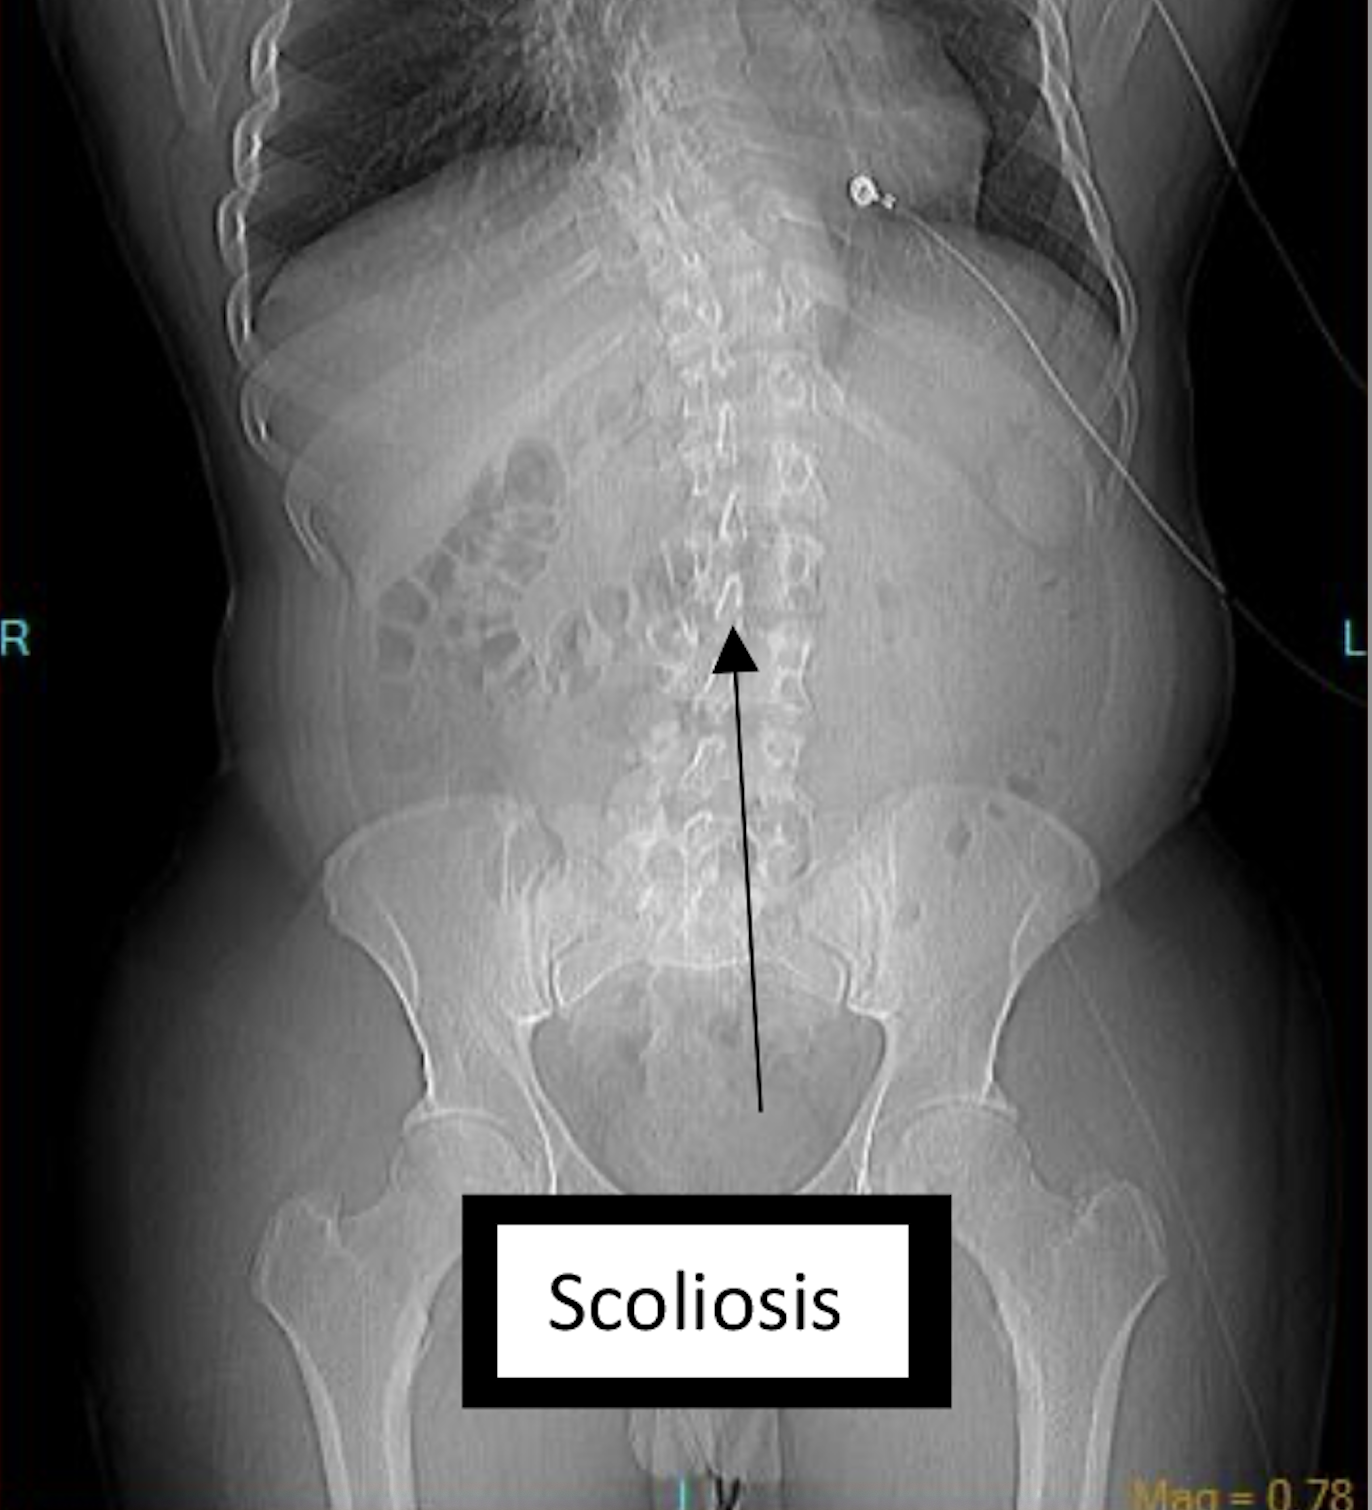

A contrast-enhanced CT scan was completed and revealed stenosis of the celiac trunk and mild bulbous dilatation of the post-stenotic celiac trunk (Figure 1). There was the appearance of a dissection flap that developed into an eccentric hypodense non-enhancing false lumen. This appeared to extend into the common hepatic arterial trunk and the splenic arterial branch, then continued to the splenic hilum (Figure 2 and Figure 3). In addition, there was a large splenic hypo-density involving almost one-third of the central spleen (Figure 4). The findings were consistent with an acute dissection of the splenic and hepatic arteries, along with splenic infarction of the central one-third of the spleen. A differential diagnosis of arcuate ligament syndrome was also considered, given the significant scoliosis seen on scout film of the CT scan (Figure 5).